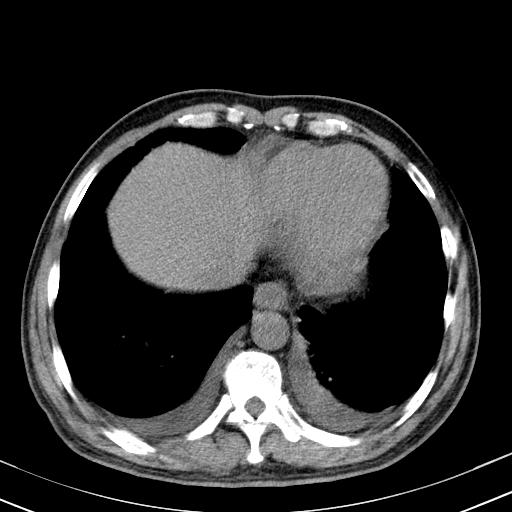

以下是引用zjzjr在2010-3-21 17:39:00的发言:[br]右下中心型肺癌并阻塞性肺炎/不张,纵膈淋巴结肿大,右侧大量胸腔积液,左侧少量胸腔积液

以下是引用zxl51642在2010-3-21 17:06:00的发言:[br]右下中心型肺癌并阻塞性肺炎/不张,纵膈淋巴结肿大,右侧大量胸腔积液,左侧少量胸腔积液,少量腹水。建议纤维支气管镜进一步检查。